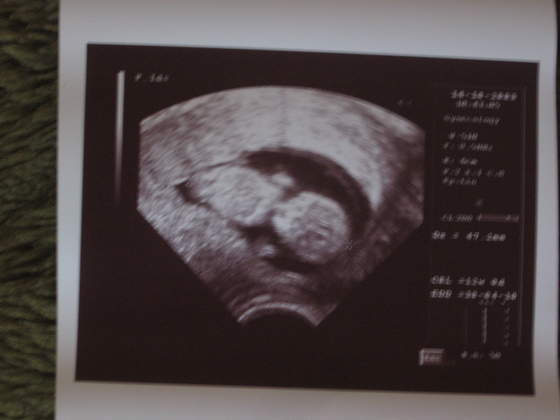

Pati od mniej wiecej tygodnia czuje jak mnie ktos smyra od srodka :-). odkrylam to przypadkiem, jak cos mnie zaswedzialo pod pepkiem i sie delikatnie podprapalam ...

i poczulam "interakcje" z drugiej strony :-)